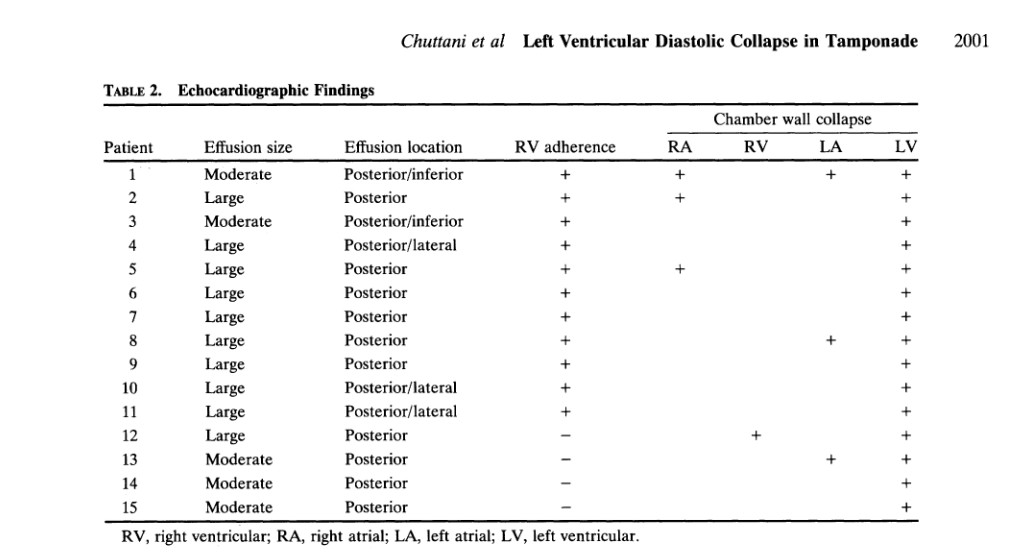

O colapso diastólico do VE foi descrito pela primeira vez por Chuttani et al., quando foi observado ser uma causa frequente de tamponamento após cirurgia cardíaca por presença de aderências entre as cavidades direitas do coração e a parede torácica, com tendência a uma localização mais posterior.